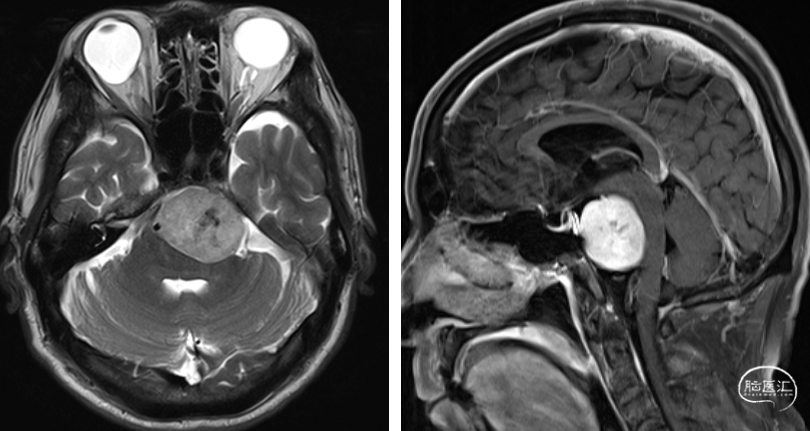

一般资料

术前检查

术前诊断